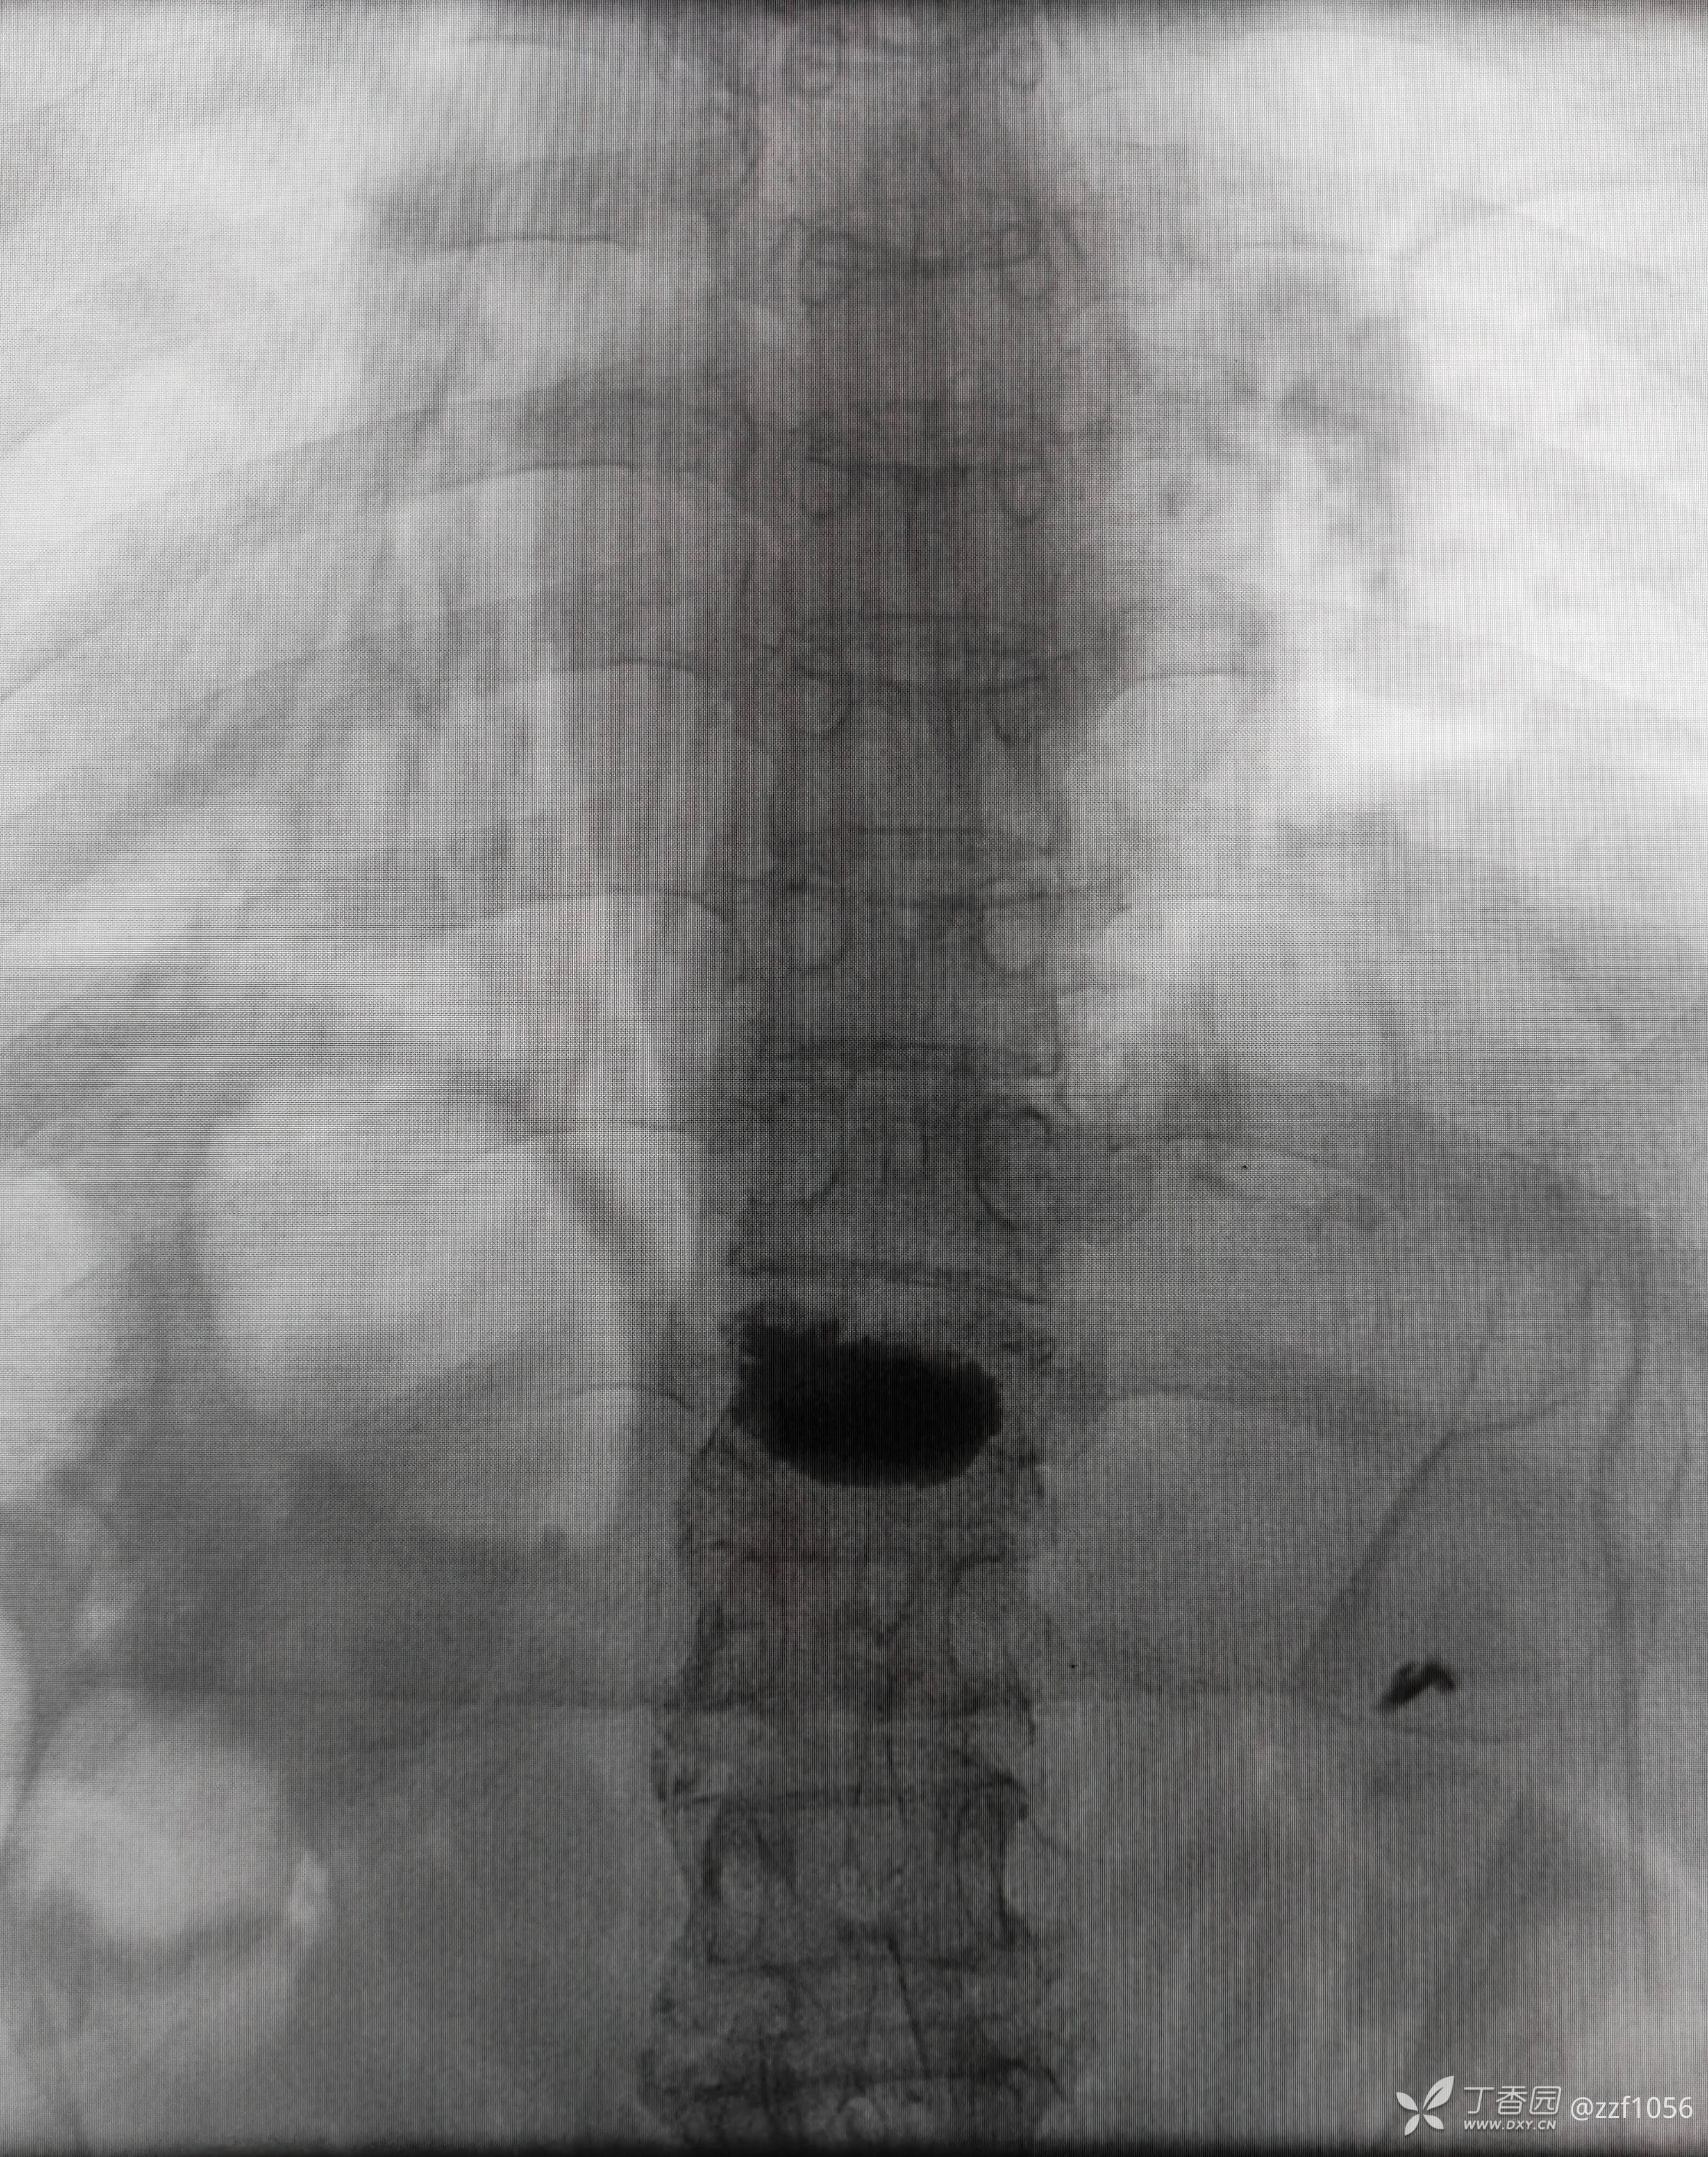

那么看术后CT

可是患者仍感觉腰痛,两个月后去B医院就诊,B医院观点是对侧再次穿刺加注骨水泥,站友们你的观点呢?

据病人描述加注后疼痛缓解

术后